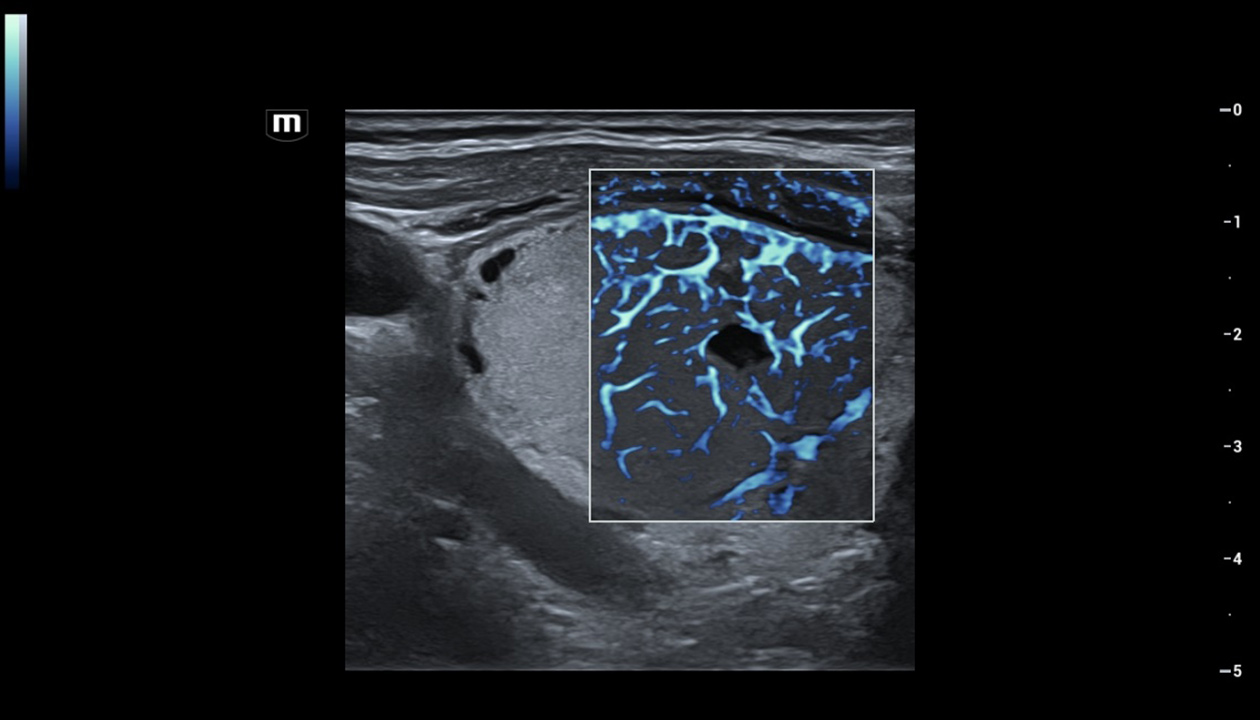

Für die Ultraschalltechnologie stellt die ZST+-Plattform einen bedeutenden Fortschritt dar, da sie statt der herkömmlichen Strahlformung die Kanaldatenverarbeitung verwendet. Diese bahnbrechende Innovation löst übliche Zielkonflikte zwischen räumlicher Auflösung, zeitlicher Auflösung und Homogenität des Gewebes auf, woraus sich eine beispiellose Bildqualität ergibt, die den Weg frei macht für unendlich viele Bildgebungslösungen.

Das Resona I9 weist umfassende klinische Lösungen für spezielle Anwendungen auf. Auf der Grundlage gründlicher Analysen verschiedener klinischer Szenarien liefert es Innovationen, die den Benutzenden herausragende Klarheit, außergewöhnliche Intelligenz und eine erhöhte Diagnosesicherheit bieten.